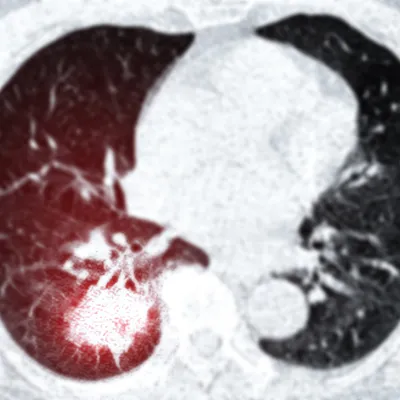

The Fleischner Criteria, provides standardized recommendations for the management of incidentally detected pulmonary nodules on CT scans. The key word here is incidentally detected, this is not to be used for LUNG RADS screening low dose CT. Fleischner guidelines help radiologists and clinicians assess the risk of malignancy and determine appropriate follow-up intervals based on nodule size, appearance, and patient risk factors. Originally introduced in 2005 and updated in 2017, the criteria aim to reduce unnecessary testing while ensuring timely diagnosis of potentially malignant nodules.

One of the key strengths of the Fleischner Criteria is its risk-based approach. The guidelines distinguish between low-risk and high-risk patients, based on factors like age, smoking history, and cancer history. Nodules are further categorized by size (typically using a 6 mm and 8 mm threshold) and morphology (solid, subsolid, or part-solid). For example, a solitary solid nodule less than 6 mm in a low-risk patient generally requires no follow-up, while a larger or part-solid nodule may require serial imaging or even tissue sampling.

These recommendations provide a structured, evidence-based pathway that helps reduce variation in care. Knowing that a nodule <6 in a low risk patient which is purely solid or ground glass really needs no specific follow up is a key takeaway. By standardizing follow-up intervals and reducing over-surveillance of benign nodules, the Fleischner Criteria help limit patient anxiety, avoid unnecessary radiation exposure, and manage healthcare costs more effectively. Conversely, nodules with suspicious features or in high-risk patients are monitored more closely, increasing the chances of early detection of lung cancer.